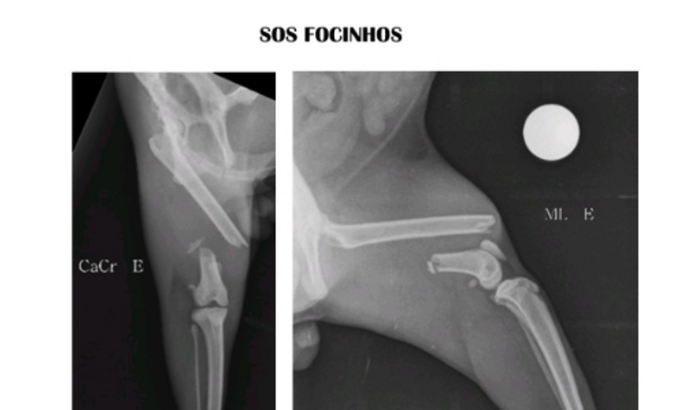

Nosso gato, Bee foi atropelado por uma moto, levamos ele correndo ao veterinário popular onde descobrimos o terrível fato de que o Bee está com o fêmur quebrado. Infelizmente estou em limbo judicial, sem receber dinheiro algum.Meu filho trabalha de freelancer, e já gastou quase todo dinheiro pagando a consulta veterinária e o raio-x quase não temos para nos manter. O caso é gravíssimo. O Bee não consegue andar e passa o dia minhando de dor e se não conseguir uma cirurgia em breve irá morrer de infecção.Em nosso desespero passamos dias procurando ajuda para nosso gatinho, mas nenhuma viva alma teve compaixão em nos ajudar. Peço por favor qualquer ajuda por menor que seja para alcançar o valor da cirurgia mais barata que não é menos de 3.500 mil reais.